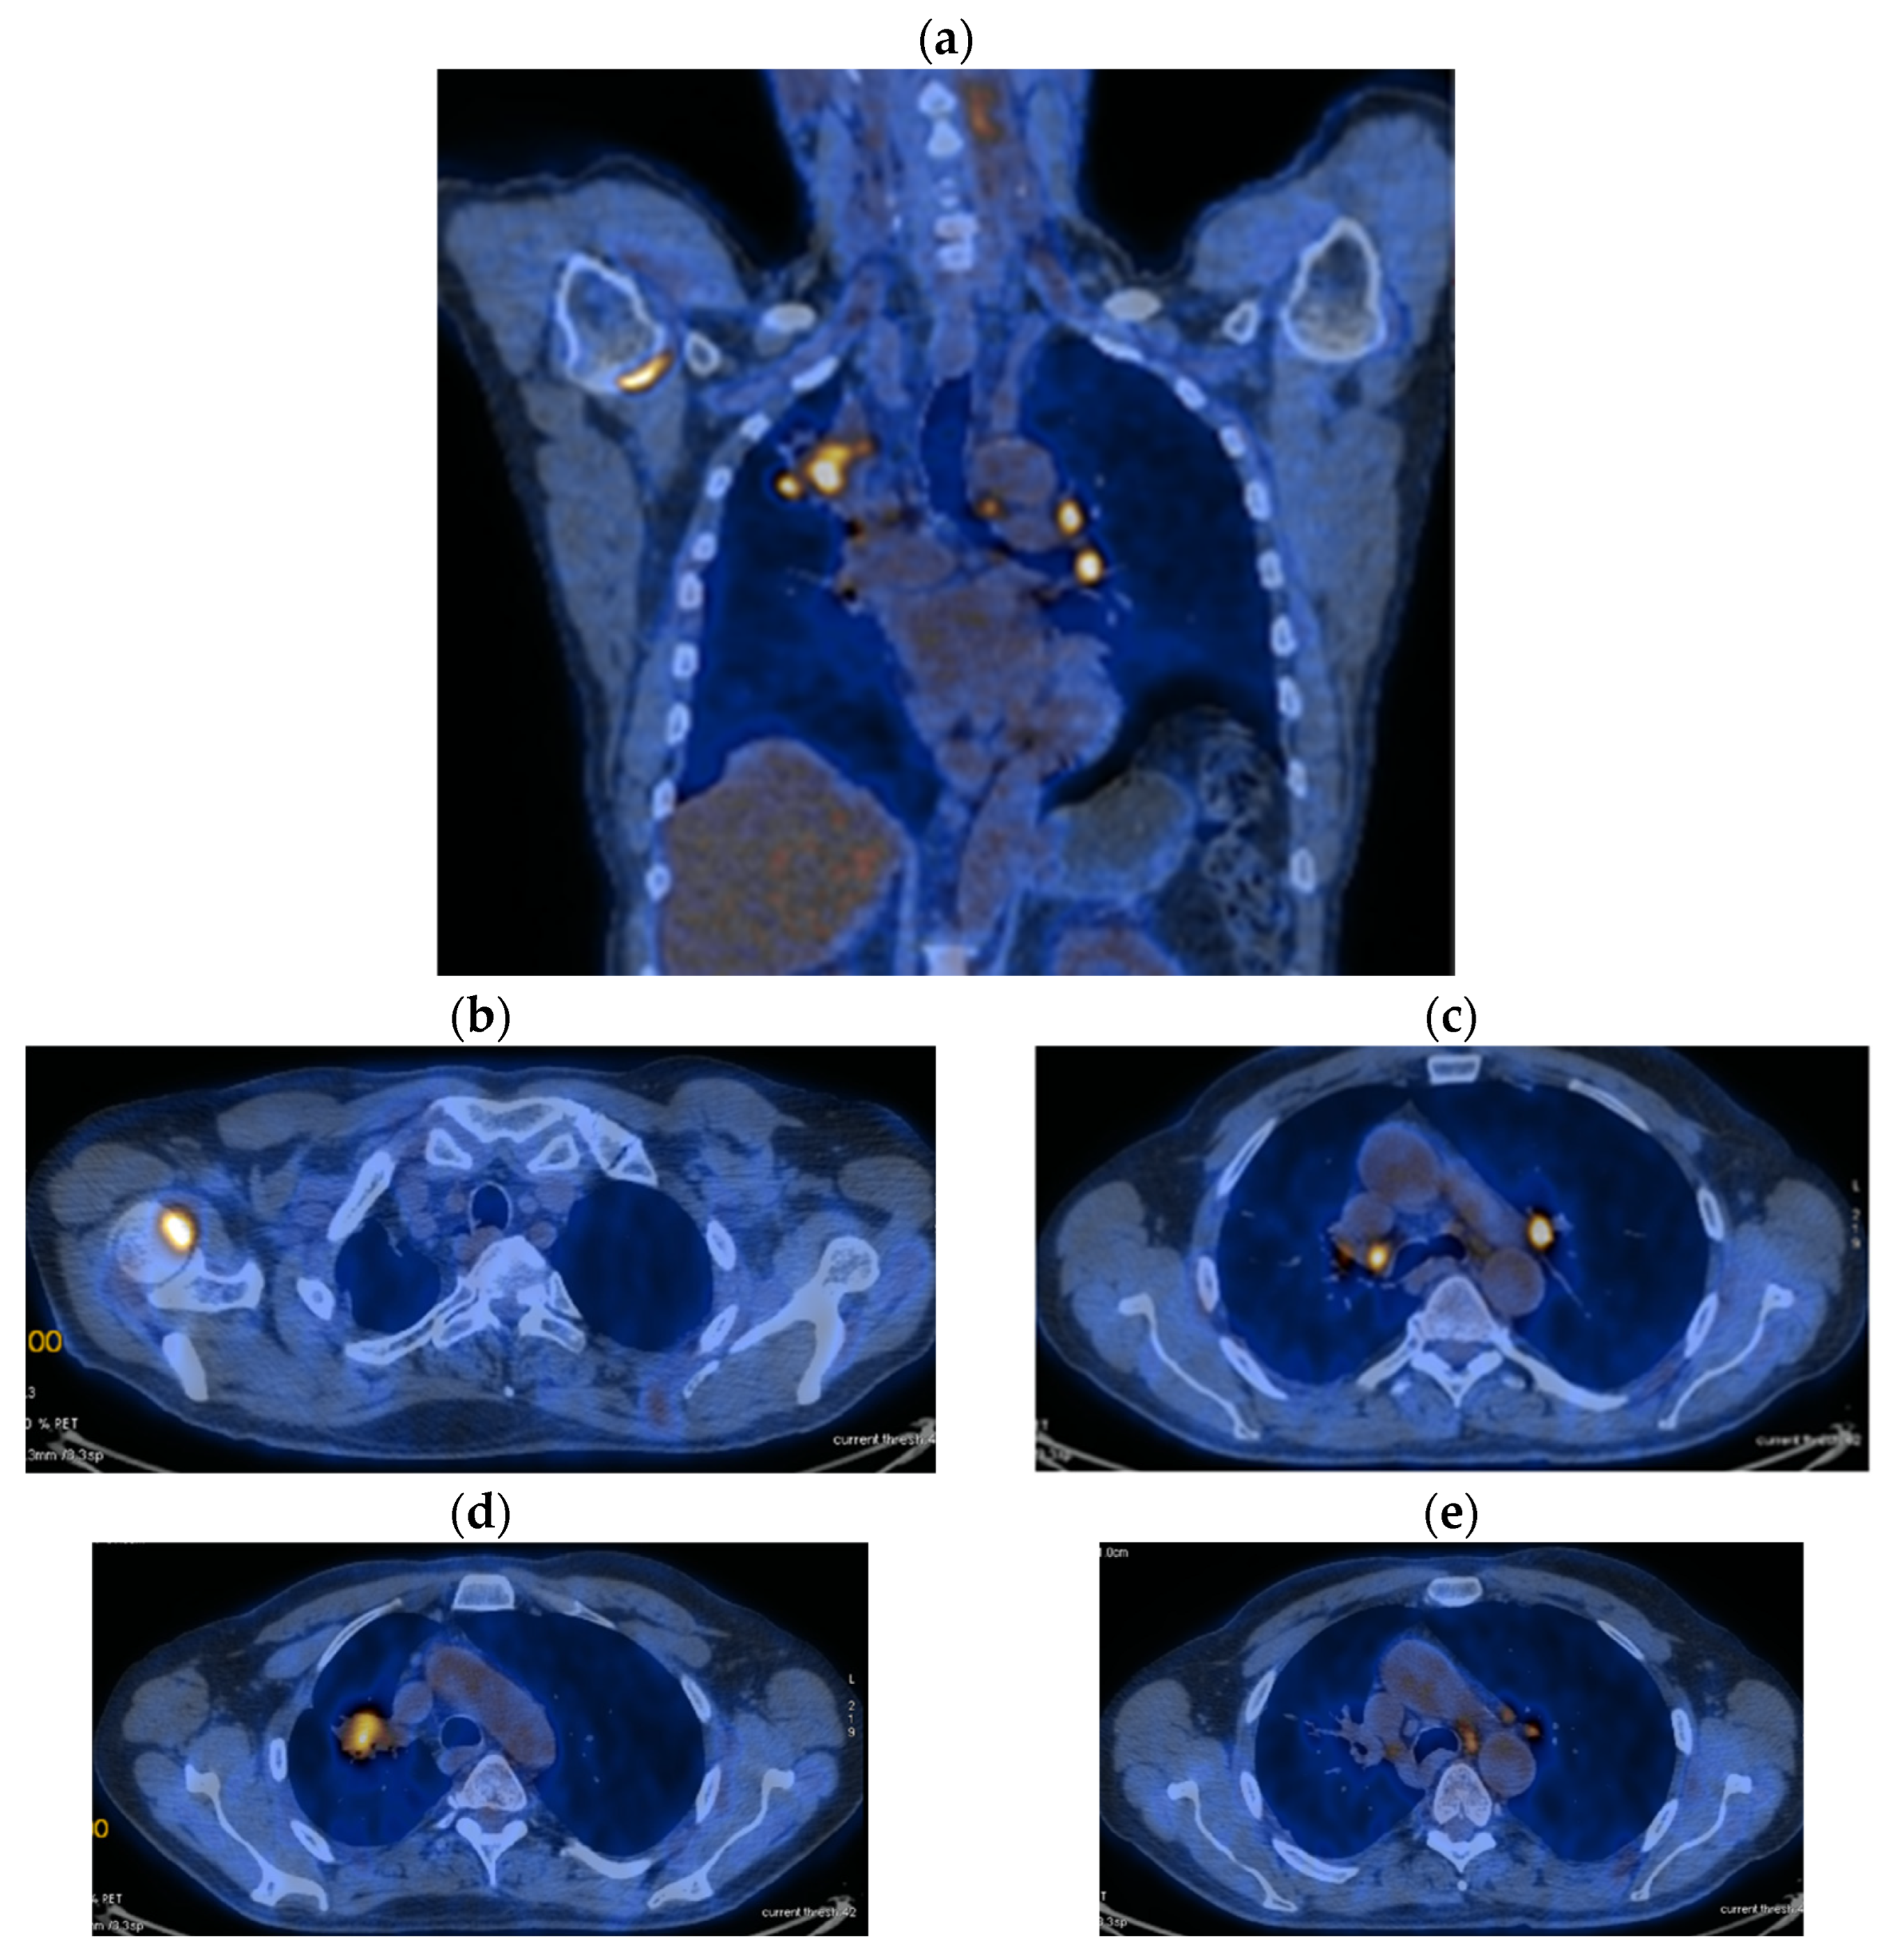

2. Case Presentation

2.2. Monitoring 2022: Oncological Commission 1910/16.08.2022

2.3. Oncological Committee 07/25/2023 Recommended

- Consider rescue re-irradiation (SBRT), taking into account the current primary tumor dimensions of 24 × 34.2 mm on PET CT from 06/2023 and also the total dose previously administered (08–09/2020), the previously applied fractionation, the time between the two irradiations, the cellular repair time and the dose constraints for the organs at risk.